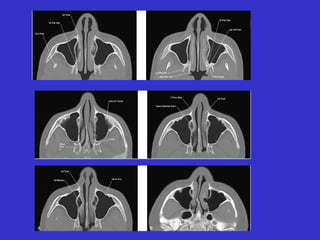

Este documento describe las diferentes proyecciones radiográficas utilizadas para examinar los senos paranasales, incluyendo las proyecciones básicas de Caldwell, Waters lateral y las proyecciones especiales como Hirtz y Waters mentonasal. También describe las diferentes estructuras anatómicas que componen el complejo ostiomeatal anterior y posterior de los senos paranasales.